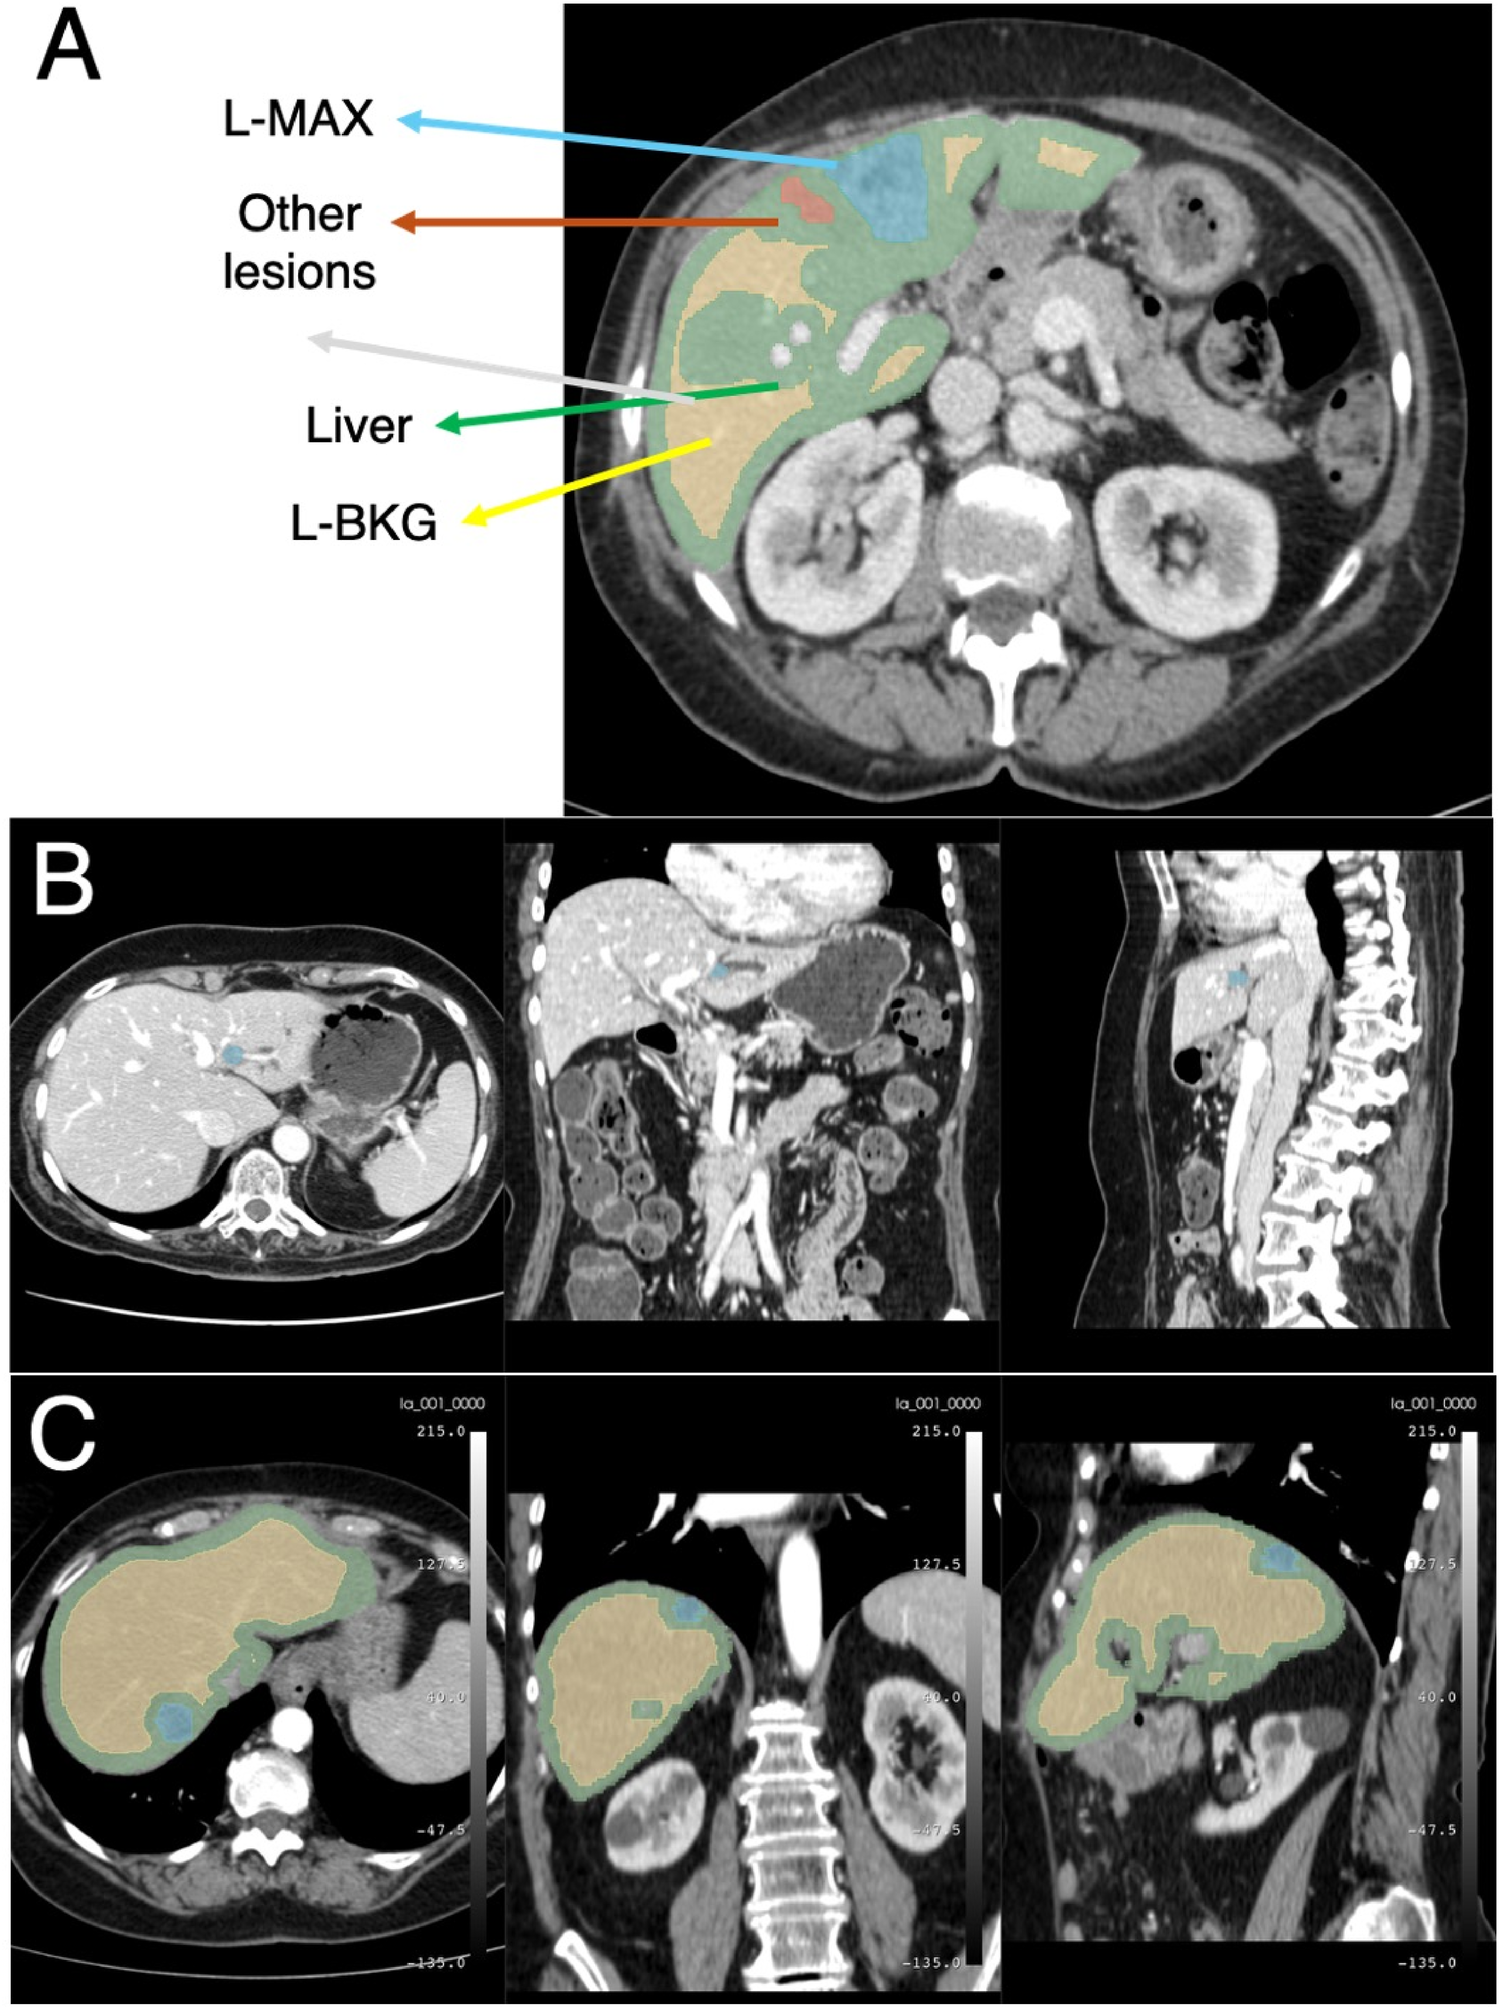

Figure 1 summarizes the proposed end-to-end workflow. After image preprocessing, radiomic features were extracted from two volumes of interest, i.e., the L-MAX and the L-BKG, for both the TCIA-CRLM and the IRE-IRCCS image series. For each cohort, two sets of features were created: (i) the L-MAX features set; (ii) the RATIO features set, obtained from the element-wise ratio between the L-MAX and the L-BKG features. Figure 2A depicts an example of CT-based segmentation of liver lesions and parenchyma. L-MAX (blue) indicates the biggest lesions; L-BKG (green) represents parenchyma, with a 5 mm border from any lesions within the liver and from the liver surface (yellow). Figures 2B,C show axial, coronal, and sagittal views of a series from the discovery and the validation set, respectively.

Example of CT images. (A) Example of CT-based segmentation highlighting the largest lesion (L-MAX) and smaller lesions, healthy liver parenchyma (L-BKG), and surrounding anatomical structures. Axial, coronal, and sagittal views from the discovery set (B) and from the validation set (C).